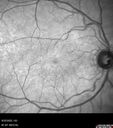

Branch Retinal Vein Occlusion - Foveal Ischemia Neovascularization Non perfusion215 views38 year old patient with a BRVO who had PRP laser for vitreous hemorrhage. Vision remained 20/160 from foveal ischemiaFeb 24, 2023